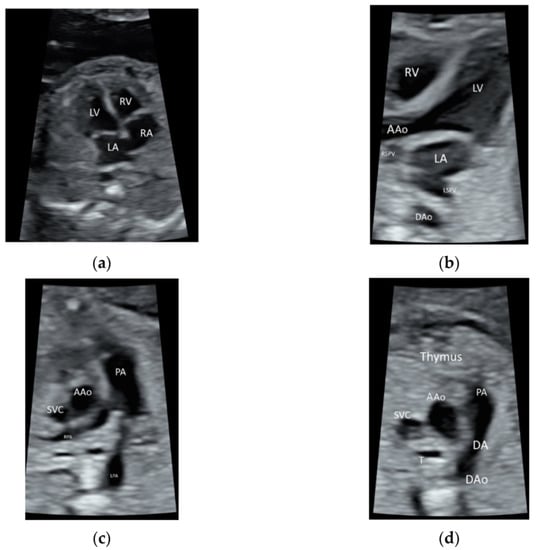

5.2. Spatiotemporal Image Correlation

5.3. 3D Ultrasound Examination of Face, Limbs, and Other Structures